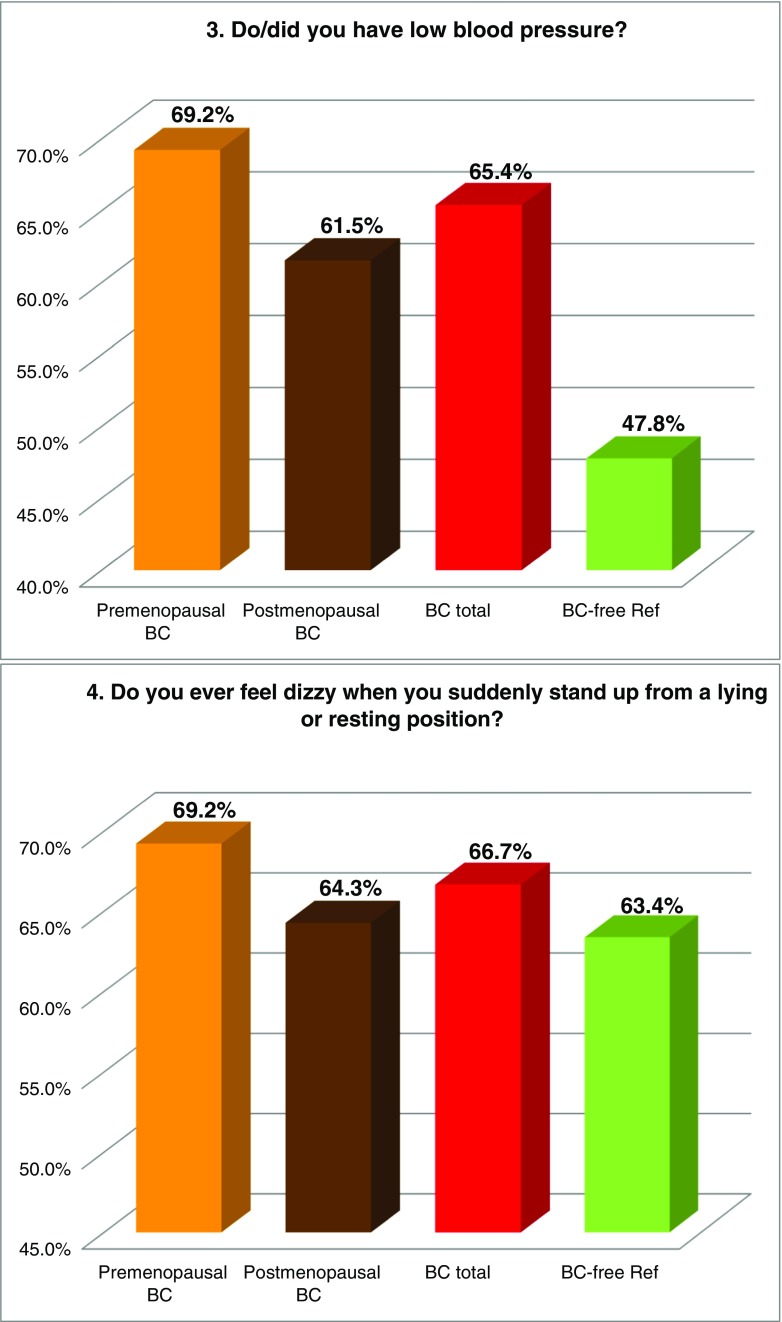

FS prevalence evaluated by individual symptoms

Figure 2 summarises the prevalence of individual “Flammer Syndrome” symptoms (1–15) in two main groups of comparison—“BC total” patients versus the reference group of “BC-free” individuals as well as in individual subgroups of BC patients subdivided according to their menopausal status. Higher prevalence in “BC total” (marked in red) has been demonstrated for all 15 symptoms investigated in this study. Statistical significance has been recorded for symptoms 1 (cold extremities), 2 (feeling cold), 5 (prolonged sleep onset), 7 (headache), 8 (accompanying symptoms), 9 (drug sensitivity) and 11 (smell perception); corresponding p values are provided in Table 3. Although being statistically non-significant (p = 0.103), a substantially greater prevalence has been demonstrated for symptom 6: “no feeling of thirst and drinking too little” the BC patients, in general, have demonstrated two times more frequently compared to the disease-free reference group; for the postmenopausal BC, this difference was even more pronounced. Also, the appearance of tinnitus (symptom 14), although being statistically non-significant (p = 0.095), was evidently more frequent in BC, particularly in the premenopausal subgroup demonstrating about two times higher prevalence compared to the disease-free reference group. Symptom 3 (low blood pressure) was more specific for the premenopausal BC demonstrating 22% higher prevalence against the disease-free reference group. In contrast, symptom 12 (low body weight in early adulthood) was more specific for postmenopausal BC. A slightly higher prevalence was demonstrated for symptom 4 (dizziness) in BC. Strong plurality has been demonstrated amongst the BC subgroups for the following three symptoms: 10 (pain, more specific for the postmenopausal BC), 13 (perfectionism, more specific for the postmenopausal BC) and 15 (skin blotches in stress, more specific for the premenopausal BC) as summarised in Table 3.

Fig. 2.

Evaluation of the prevalence of individual symptoms (1–15) of the “Flammer Syndrome” phenotype in two groups of comparison: “Breast cancer diseased” (BC total) versus “Breast cancer-free” reference (BC-free Ref) groups. Therein, the entire breast cancer patient pool (“BC total”) has been additionally analysed in subgroups stratified according to the menopausal status of the patients. For more details regarding the patient’s recruitment and stratification, see “Materials and methods” section. The prevalence in each individual group is presented by percentage of individuals who have responded to the corresponding question with “frequently” and “sometimes” pooled together. Responders answering with “I do not know” have been excluded from the overall numbers/calculations. Question-specific notes: question 6—the ratio between “I do not feel thirsty and drink little” and “I feel much thirsty and drink a lot” has been calculated and expressed as X times; question 12—answers “very slim” and “slim” are pooled together and presented in percentage

Table 3.

Symptoms of the “Flammer Syndrome” recorded in “Metastatic breast cancer patients” versus “Breast cancer-free individuals” groups of comparison

The table summarises the results demonstrated in Fig. 2; the following system is employed: “+” means higher prevalence of the corresponding symptom (above the lowest average of the groups of comparison); “−“ means lower prevalence of the corresponding symptom (lowest average and below it); “++“ means values sufficiently over the highest average. All 15 symptoms demonstrate increased prevalence in BC total versus BC-free. The level of significance is noted: p values below 0.05 are considered statistically significant and marked in red colour (symptoms 1, 2, 5, 7, 8, 9, 11). Thirteen symptoms united within the green-marked cluster demonstrate the prevalence ultimately increased in BC total as well as BC subgroups. Although the prevalence of symptoms 13 and 15 (yellow-marked cluster) is slightly increased in “BC total” compared to “BC-free,” it varies in BC subgroups demonstrating a particularly strong plurality amongst the patients with the metastatic BC investigated in the current study

The meaning of individual FS symptoms specifically for the BC patient cohort has been discussed in detail in the recently published article “Breast Cancer and Flammer Syndrome: Any Symptoms in Common for Prediction, Prevention and Personalised Medical Approach?” [28]. Current chapter emphasises a particular relevance of the FS symptoms for the metastatic disease in the BC patient cohort: all 15 symptoms demonstrate the prevalence in the metastatic BC versus BC-free reference group with a statistical significance (p ≤ 0.05) for seven symptoms as summarised in Table 3. Other symptoms, even being statistically non-significantly prevalent within this study, can be of great importance for the BC pathology and metastatic disease. Hence, symptom 3 (low blood pressure, p = 0.127) is particularly relevant for the premenopausal subgroup and may strongly contribute the cardio-vascular component characteristic for the FS as explained above. Another example is the following: symptom 4 (dizziness, p = 0.762) has been described earlier as being permanently present and stepwise worsening in BC followed by metastasis in the brain [20, 33]. Finally, the normal feeling of thirst (symptom 6, p = 0.103) is extremely important and if diminished (here two times in BC versus BC-free) plays a crucial role in the body dehydration and BC development [20].